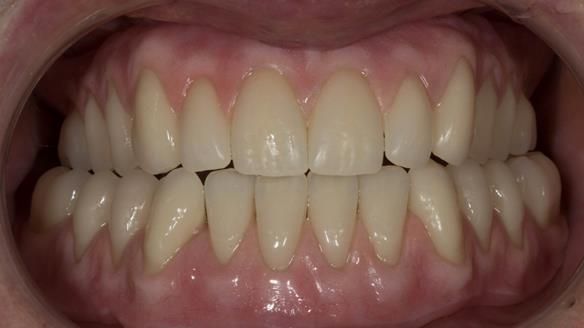

This newsletter describes in step by step detail the provision of a lower implant supported metal based complete denture with three dental implants positioned in the anterior mandible. The upper arch was restored with a metal based complete upper denture.

"An improvment in appearance would also be appreciated."

I provided new metal based complete dentures. The clinical situation and treatment process is shown in detail below with photographs. I provided the clinical work and Rowan Garstang provided the technical work. The dentures took 5 visits to make - with the patient travelling by plane from Ireland to Manchester. The patient had one review after the dentures were fitting.